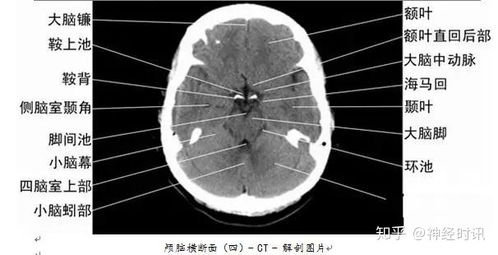

CT系统在医学影像领域具有广泛的应用,主要包括以下方面:

诊断疾病:CT扫描可以用于诊断多种疾病,如骨折、肿瘤、心脏病等。